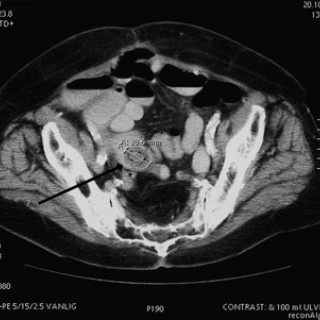

En 23 år gammel førstegangsgravid kvinne som fra tidligere stort sett var frisk, ble innlagt i lokalsykehus ved svangerskapslengde 22 uker + 2 dager, med en seks dagers sykehistorie med generell sykdomsfølelse, feber opptil 40 °C, kvalme, oppkast og anoreksi. I tillegg hadde hun fått økende ansiktsødemer, korsryggssmerter, hodepine og synsforstyrrelser. Svangerskapet hadde vært ukomplisert frem til det aktuelle. Hun var normotensiv. Blodprøvene viste kreatinin 236 µmol/l, karbamid 13 mmol/l, urat 410 µmol/l, leukocytter 15,0 · 10⁹/l, CRP 106 mg/l og trombocytter 86 · 10⁹/l. Leverprøvene var...